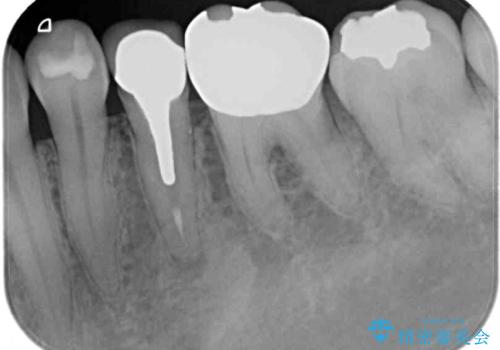

- 奥歯の銀歯をセラミックの白い歯にして、しみる症状も改善したいとのことで来院された患者様です。

知覚過敏の症状が強い歯と、銀歯の範囲や銀歯の下のむし歯が大きい歯は、インレー修復では対応が難しいためオールセラミッククラウンで、インレー修復で対応が可能な歯ではセラミックインレーにて修復することとしました。